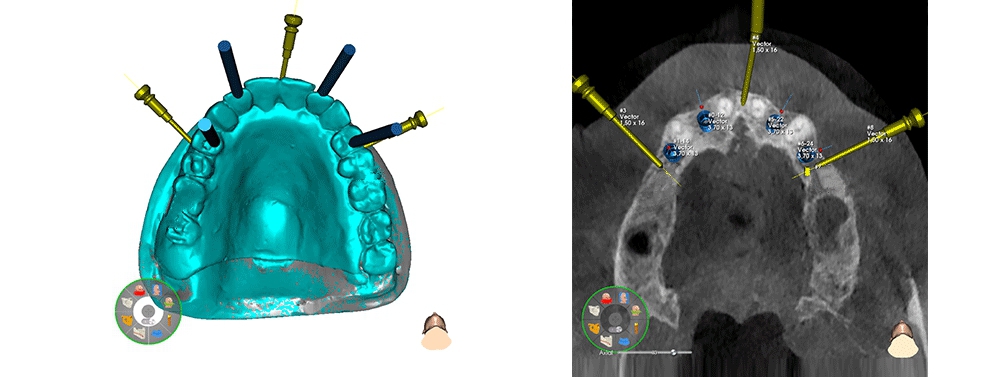

TAC con Universal Stent

Pianificazione del numero e sede degli impianti

Realizzazione della dima chirurgica